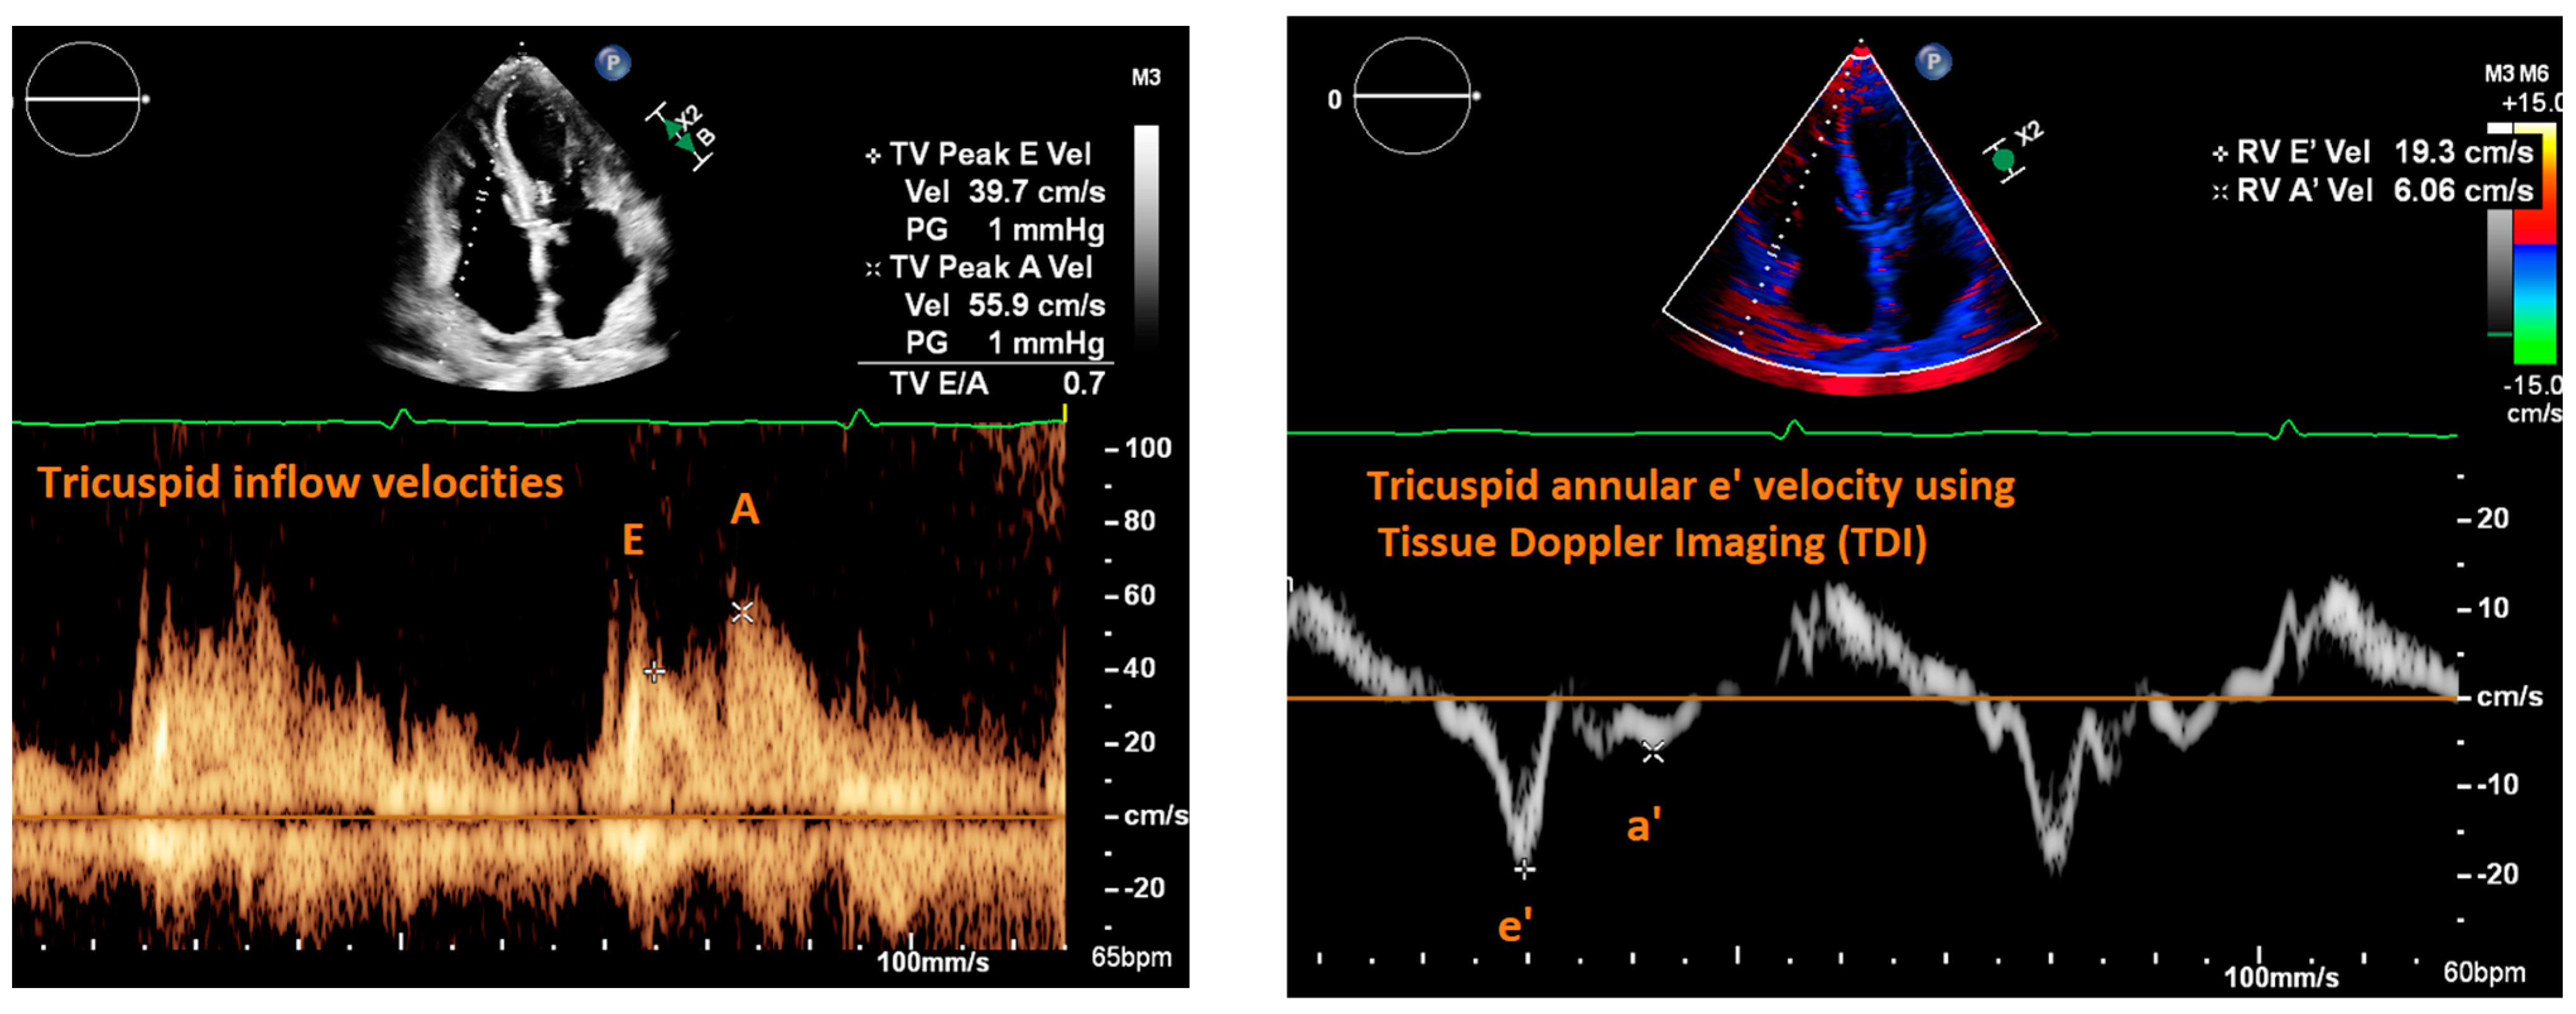

2. Cardiac Ultrasound

| Fletcher et al., 2020 [9] | Systematic review | Tricuspid inflow velocities | Patients with valvular disease, altered RV systolic function, recent cardiac surgery, acute heart failure, heart transplant, pulmonary hypertension, atrial fibrillation | Strength of correlation between E/e’ and RAP | 17 articles | Consistent positive correlation between E/e’ and RAP in patients with reduced RV systolic function; equivocal support correlating E/e’ and RAP in heart failure patients. |

| Modality | Measure | Normal Range | Interpretation | Limitations |

| Cardiac Ultrasound | ||||

| Mitral E/e’ ratio estimated from the E wave velocity of the mitral inflow Doppler envelope and the tissue Doppler e’ wave velocity at the mitral annulus (septal and/or lateral) | E/e’ ≤ 14 |

|

| |

| DT in the mitral inflow Doppler envelope | 160–200 ms |

| Peak velocity of the TR jet | ≤2/8 m/s |

| Estimated PASP using TR jet plus estimated RAP from IVC assessment | ≤35 mmHg |